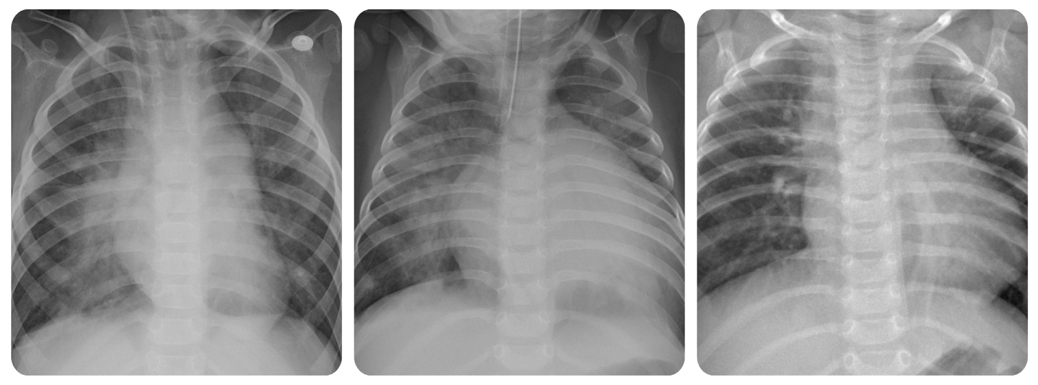

본 연구에서는 학습 데이터 5,216장(정상 1,341장, 폐렴 3,875장), 테스트 데이터 624장(정상 234장, 폐렴 390장)으로 구성된 ChestXRay2017 Dataset[9]을 사용하였다. 해당 Dataset은 주로 1~5세 소아 환자의 흉부 X-ray 영상으로 구성되어 있다. 그림 7은 정상 환자의 흉부 X-ray 예시 이미지를, 그림 8은 폐렴 환자의 흉부 X-ray 예시 이미지를 나타낸다.

Fig. 7.

Chest X-ray images of normal-class children

소아 X-ray 영상은 성인과 비교할 때 뚜렷한 해부학적‧영상학적 차이를 보인다. 예컨대, 소아는 해부학적으로 흉곽 크기가 작고, 연조직 발달이 미흡하며, 뼈조직의 석회화가 완전히 이루어지지 않아 X-ray의 투과도가 성인에 비해 높다. 그 결과, 폐 실질의 혼탁과 폐렴 병변에 의한 음영 증강 등 구조 변화가 영상 상에서 더욱 명확하게 드러나게 된다. 이러한 점은 폐렴 병변의 위치와 확산 형태를 비교적 선명하게 관찰할 수 있게 하며, 이는 인공지능 모델이 소아 영상에 대해 상대적으로 높은 진단 민감도와 특이도를 달성할 수 있는 잠재적 이점을 제공한다.

임상적으로도 소아와 성인 폐렴은 영상 소견에서 차이를 보인다. 소아 폐렴은 주로 폐포성 병변이 많고, 폐 실질의 뚜렷한 음영 증가 및 침윤이 영상에서 직접적으로 나타난다. 이에 반해, 성인 폐렴은 간질성 침윤 패턴, 기저 폐질환(만성 폐쇄성 폐질환, 폐 섬유화 등) 동반, 노화에 의한 해부학적 변화 등이 복합적으로 작용하여 영상의 비특이성과 구조적 복잡성이 커지는 경향이 있다. 이러한 성인의 해부·병리학적 요인은 실제 진단 과정에서 영상 판독 일관성과 정확도를 저하시킬 수 있다.

또한, 성인은 만성 폐쇄성 폐질환(COPD), 심부전, 폐 섬유화 등 다양한 만성 질환의 기저 질환을 보유할 수 있으므로, 폐렴 병변이 다른 구조물과 중복되거나 명확한 경계 없이 복합적으로 나타나는 경우가 많다. 반대로, 소아 환자는 기저 질환이 거의 없고, 영상 상에 단독 병변이 드러나는 경우가 상대적으로 많아 딥러닝 기반 진단 모델의 성능 산출에 유리한 환경을 제공한다.